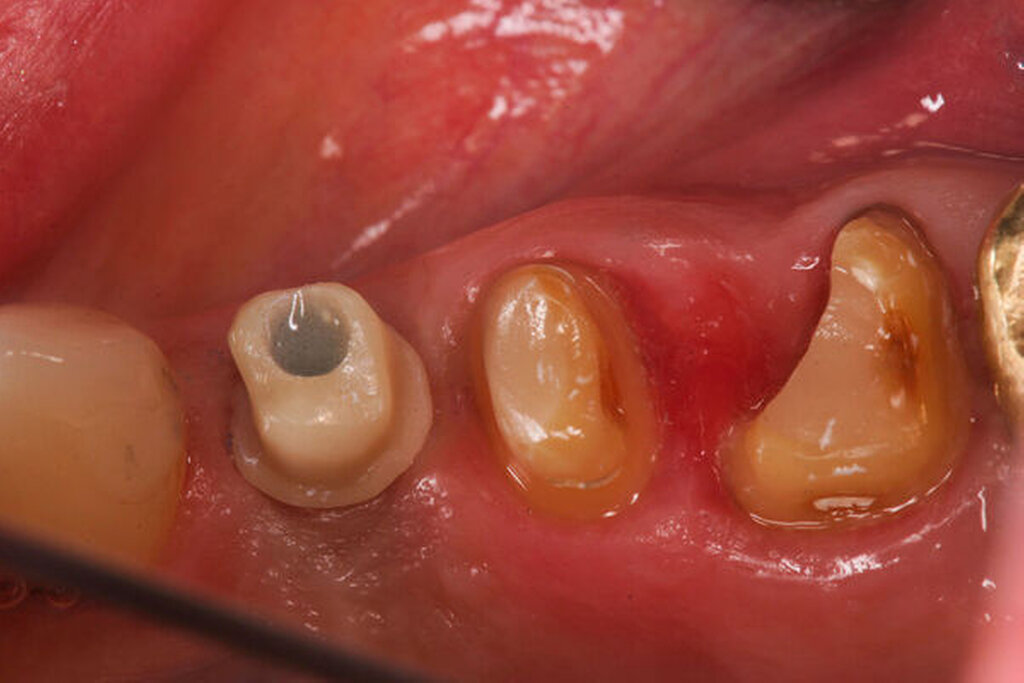

Eine 46-jährige Patientin klagte 2014 über wiederkehrende Beschwerden an Zahn 16, die sich auch nach einer endodontischen Behandlung nicht besserten. Wiederholt waren submuköse Abszesse aufgetreten. Lokalisiert war die Sondierungstiefe stark erhöht, was auf eine Längsfraktur der mesiobukkalen Wurzel hindeutete. Die Patientin wurde über die Möglichkeiten der Amputation der mesiobukkalen Wurzel sowie alternativ der Extraktion des Zahnes aufgeklärt und entschied sich für den Versuch des Zahnerhalts mittels Teilamputation der mesiobukkalen Wurzel.

Im Rahmen der Versorgung erfolgte auch ein Austausch der Extensionsbrücke 16–14 durch Einzelkronen auf 16 und 15 sowie einer Implantatversorgung mit Einzelkrone in Regio 014. Der Erhalt des Zahnes 16 ermöglichte so eine wenig invasive Versorgung des ersten Quadranten mit guter Hygienefähigkeit. Alternativ wäre bei Extraktion des Zahnes die Versorgung beispielsweise mit einer ausgedehnten Brückenkonstruktion von 13–17 oder einem weiteren Implantat in Regio 016, vermutlich mit (indirektem) Sinuslift, notwendig gewesen. So konnte der Fall minimalinvasiv zufriedenstellend gelöst werden. Die Patientin ist seit dem Eingriff beschwerdefrei und kommt gut zurecht. Die Situation ist nun seit sechs Jahren stabil.